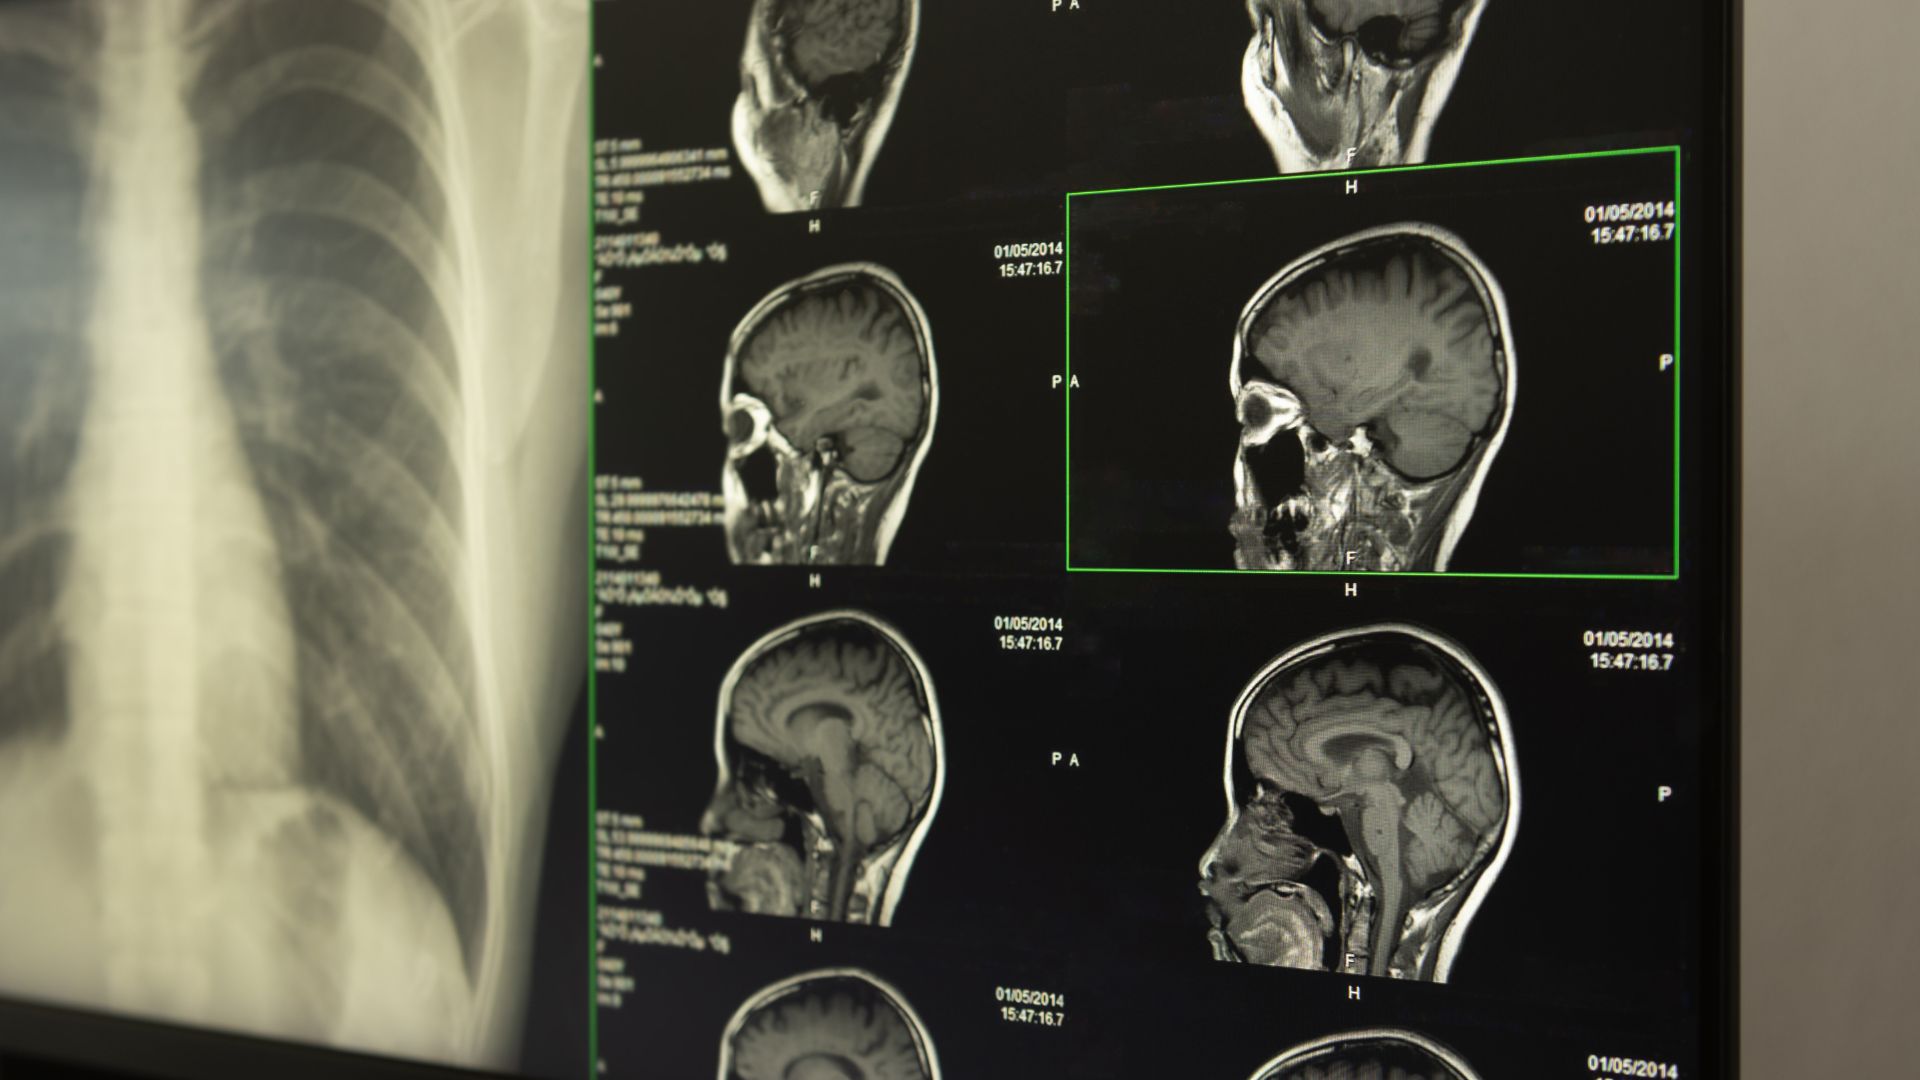

Achieving Total Resection and Minimizing Recurrence Risk for All Meningioma Grades and Locations.

High-Grade Resection Rates for All Meningioma Types

Specialized Expertise in Complex Skull Base Meningiomas